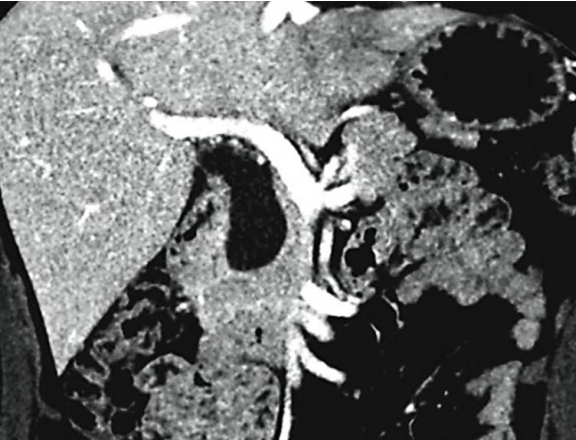

O achado de imagem a seguir corresponde a: